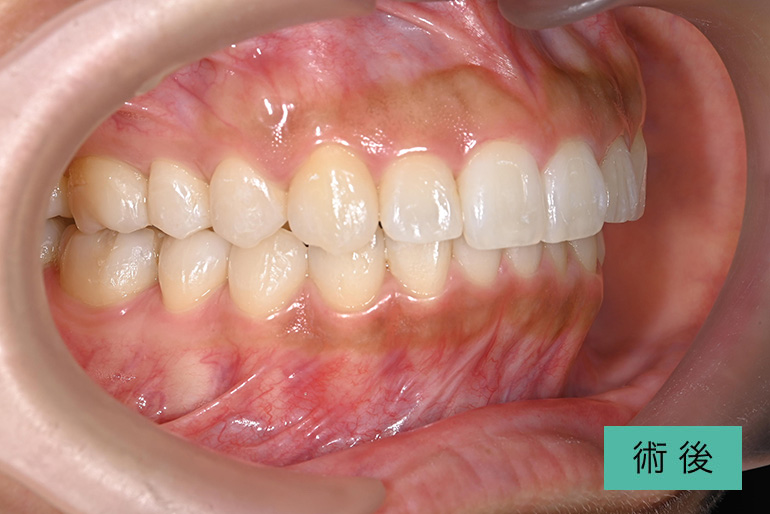

オールセラミック②

| 治療内容 | 上顎前歯右上3番から左上3番のセラミック冠 |

|---|---|

| 治療期間・回数 | 約1ヶ月、3回 |

| 費用(税込) | ¥990,000(165,000/1本)(補綴費用) ※自由診療 |

| リスク・副作用 | 疼痛、補綴物の脱落、咬合違和感、破折 |